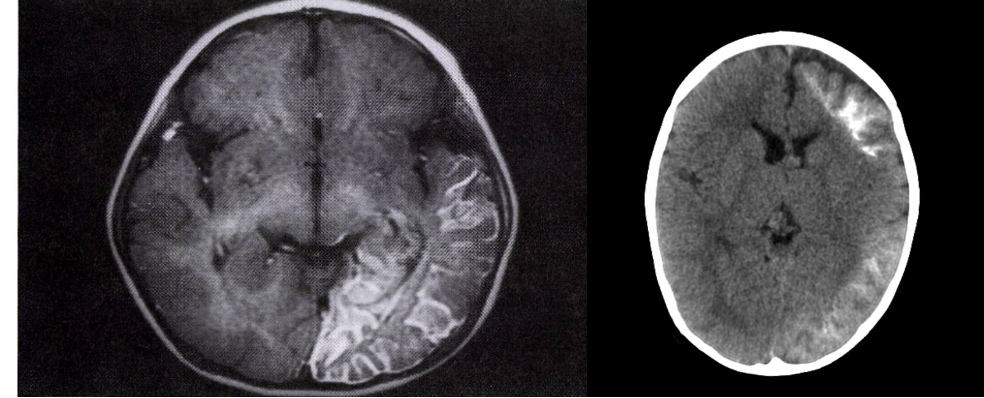

• 영상 소견: 뇌경막 혈관종, 동측의 뇌위축, 백색질이상, 뇌실질의 석회화